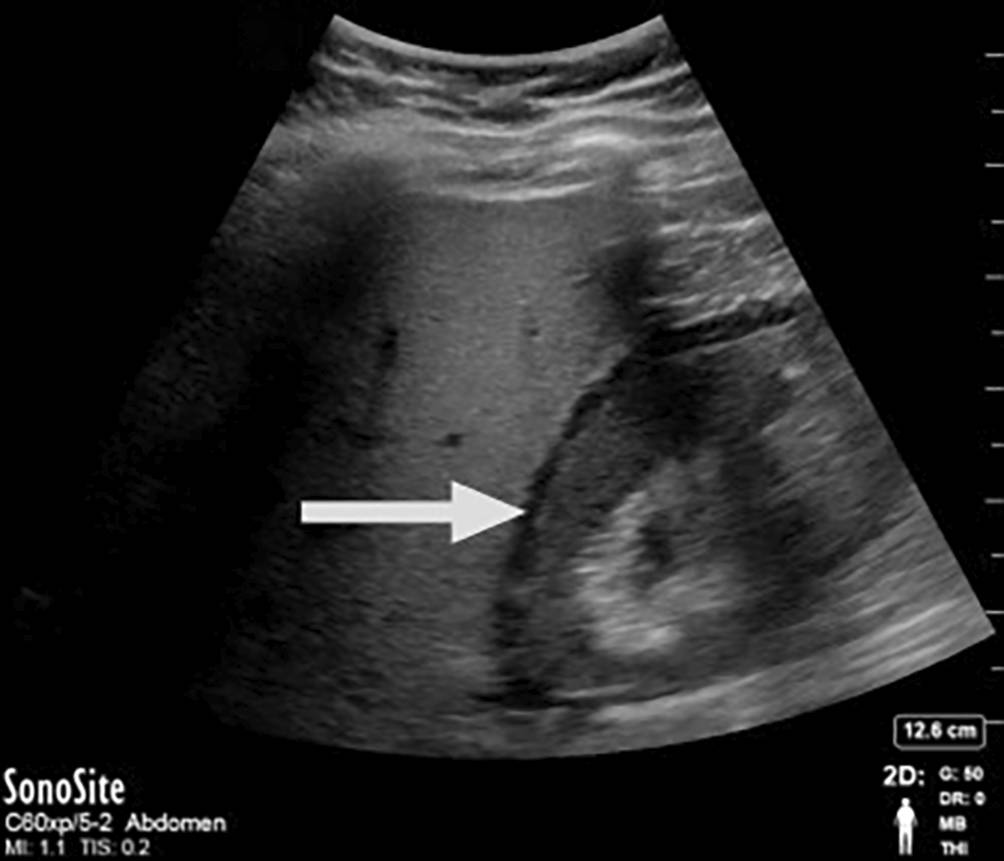

Bei einer akuten Harnstauung im Rahmen eines symptomatischen Steinleidens, postoperativ nach z. B. Nierenteilresektion oder nach einem Nierentrauma kann es zur Fornixruptur mit Urinleckage kommen und sich ein Urinom ausbilden. Bleibt die zeitnahe Diagnose oder das angemessene Management (aktive Überwachung, Ableitung, Antibiotikatherapie) aus, kann es zu Komplikationen wie Elektrolytstörungen, Abszessbildung oder Urosepsis kommen. Urinome manifestieren sich sonographisch als echoarme bzw. -freie randsaumartige Flüssigkeitskollektionen perirenal oder im Sinus hepatorenalis (s. Bild 10; Abb. 2).

Abb. 2

Urinom: echoarme randsaumartige Flüssigkeitskollektionen perirenal bzw. im Sinus hepatorenalis. (Mit Genehmigung aus [16])